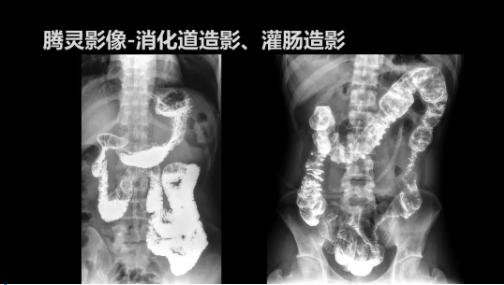

“騰靈”是安健科技的第四代動態(tài)DR產(chǎn)品,可實現(xiàn)全科室應(yīng)用。如各類常規(guī)的X線檢查、消化道檢查、骨科檢查、婦科、兒科檢查等。此外,安健科技為“騰靈”在真正意義上實現(xiàn)多科室、多功能診斷進行了多項針對性設(shè)計。